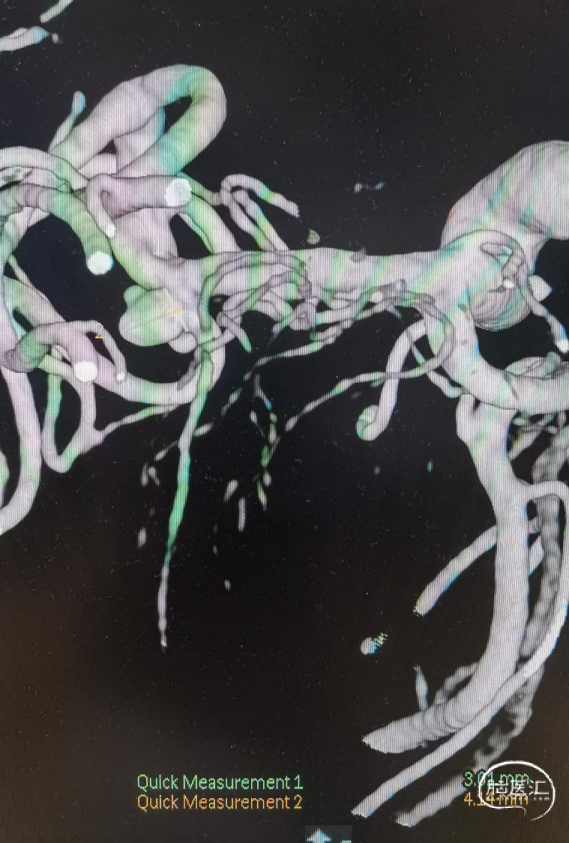

术前影像

CT显示广泛蛛网膜下腔出血,右侧侧裂池为著。

DSA示:右侧大脑中动脉分叉上干起始部宽颈动脉瘤,呈不规则分叶状,载瘤动脉管径纤细,角度锐利,载瘤动脉直径1.45mm,大脑中动脉直径2.26mm,动脉瘤大小约5.35mm×3.98mm×4.14mm。

术中全身肝素化,6F DA导引导管到达颈内动脉C1段远端,根据3D图像选取工作角度造影充分暴露载瘤动脉、瘤颈、动脉瘤长径。